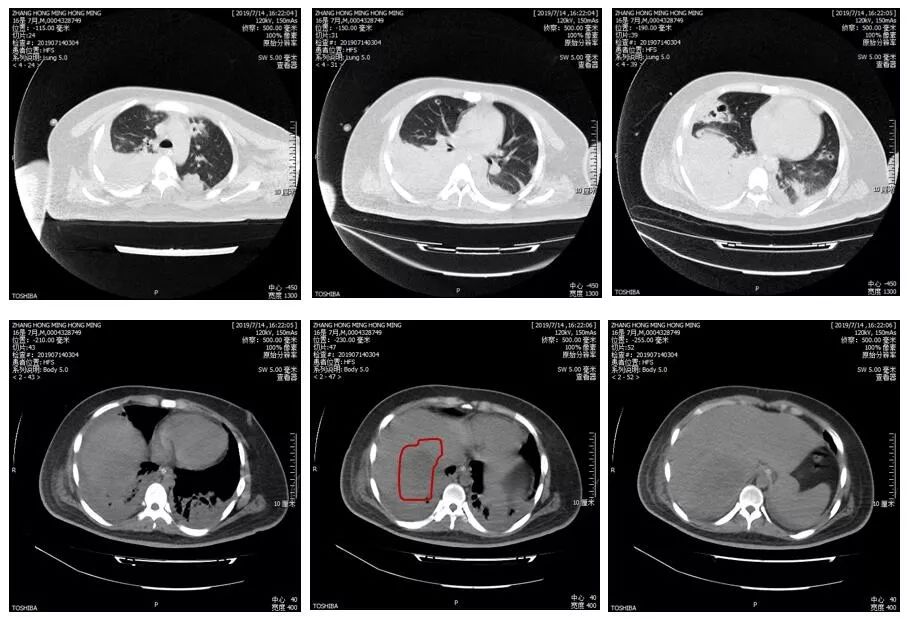

现病史:患者男性,16岁,学生,内蒙古赤峰市人,主因间断发热1个月于2019-8-1入院。患者1个月前无明显诱因出现高热、寒战,体温最高39.8℃,伴纳差、恶心、呕吐,呕吐物为胃内容物,无意识障碍、呼吸困难、腹痛、腹泻、乏力等,于当地社区卫生服务站应用“头孢类药物+炎琥宁”治疗2天无效。27天前因鼻出血不止于当地医院查PLT 10×109/L、血GLU 35mmol/L、尿酮体(+),收入当地医院ICU,进一步查胸腹部CT:双肺沿支气管血管束多发分布的结节影,肝脏多发低密度影,给予“头孢唑肟+万古霉素+奥硝唑”(具体剂量不详)抗感染治疗。25天前仍高热、寒战,出现烦躁、呼吸困难,给予镇静治疗,并行气管插管、呼吸机辅助呼吸。23天前调整抗感染治疗方案为“舒普深+万古霉素+奥硝唑”。21天前复查胸腹部CT:双肺之前多发结节影演变为空洞,有部分结节融合实变,双下肺实变、肺不张、胸腔积液,肝脏多发低密度影(密度较前减低)。患者病情持续进展,于17天前转入我院本院呼吸四部。查血常规:WBC 16.94×109/L、NE 90.7%、HGB 97g/L、PLT 405×1012/L;CRP >200mg/L、ESR 108mm/h、PCT 1.05ng/ml;血G试验、GM试验阴性;痰涂片及培养(细菌、真菌、结核、病毒)均未见异常;肝肾功能:ALB 33.3g/L、UREA 7.98mmol/L、CREA 51.5mmol/L、GLU 19.19mmol/L;血培养阴性;头胸腹盆CT平扫:1.颅脑CT平扫未见异常 2.气管插管术后改变 3.双肺多发团片小空洞性病变,考虑炎性病变,请结合临床 4.双肺下叶不张及实变,双侧胸腔积液 5.肝右叶大团块低密度灶,建议增强进一步检查(图5)。考虑存在脓毒症、肝脓肿、重症肺炎,给予“美罗培南1.0g Q8h”抗感染治疗。14天前行气管切开术并联合“阿米卡星0.8g Qd”加强抗感染治疗。入院后多次血培养均阴性,支气管镜下留取BALF送检细菌培养:肺炎克雷伯菌(敏感)、鲍曼不动杆菌及铜绿假单胞菌,余真菌、病毒、结核等相关检查均阴性。动态监测肝脏超声,肝脓肿未充分液化,未行脓肿穿刺引流。依据药敏结果,调整抗感染方案为“头孢哌酮舒巴坦3.0g Q8h联合阿米卡星0.8g Qd”。11天前出现右眼视力下降,请眼科会诊考虑右眼内源性眼内炎,给予“醋酸泼尼松滴眼液+阿托品眼膏+左氧氟沙星滴眼液”治疗,建议病情稳定后手术干预。经过抗感染、降血糖、营养支持等综合治疗,患者体温正常,意识清楚,拔除气管插管,仍有咳嗽、咳痰,右眼视力下降,转呼吸普通病房继续诊治。

图5 病例2胸腹部CT平扫(2019-7-14)